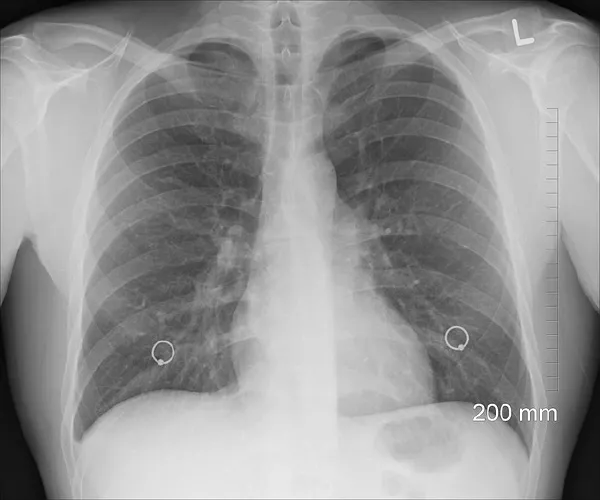

胸片检查是诊断肺炎的重要手段,通过胸片可以直观地观察到肺部是否存在炎性病变。疑难病例还可能需要进行CT检查以进一步明确病变范围和性质。